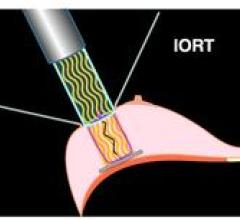

June 9, 2010 - A single radiation dose during intraoperative radiotherapy (IORT) is at least as effective as longer post-operative treatments, according to results from a study presented at the American Society of Clinical Oncology (ASCO) meeting, held June 4-8 in Chicago and published in the Lancet June 5.